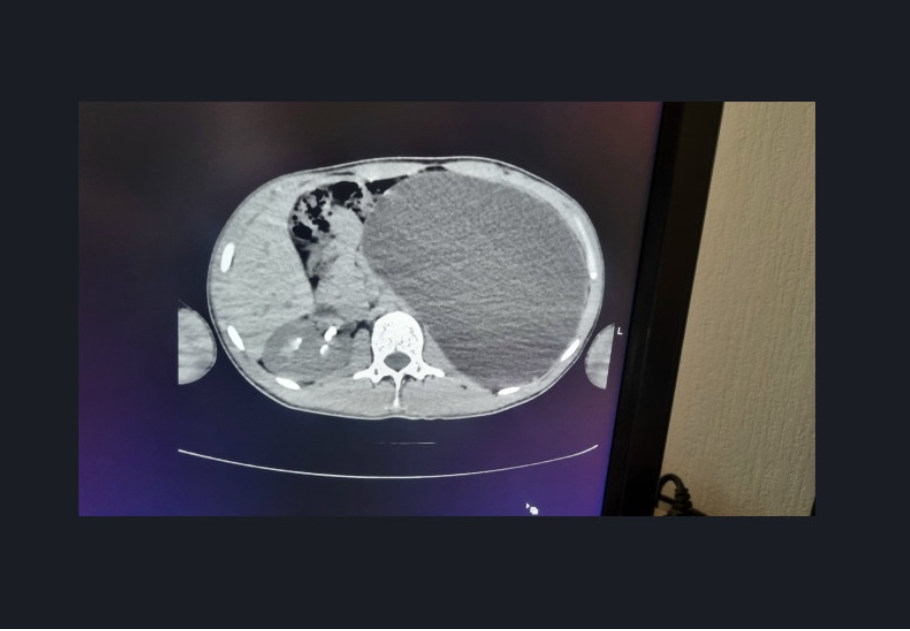

El joven, que se sentía completamente sano y nunca había tenido molestias, se sometió a un examen médico obligatorio previo a su contratación. Para su sorpresa, los médicos descubrieron que padecía hidronefrosis, una enfermedad que había inflamado su riñón izquierdo de forma descontrolada. El órgano ocupaba casi todo el abdomen y presionaba el resto de órganos.

“Era una verdadera bomba de relojería“, explicaron los especialistas del hospital. “Cualquier traumatismo, cualquier golpe accidental en el abdomen podría haber provocado una ruptura interna”. La enfermedad era asintomática y el chico ignoraba por completo el peligro.